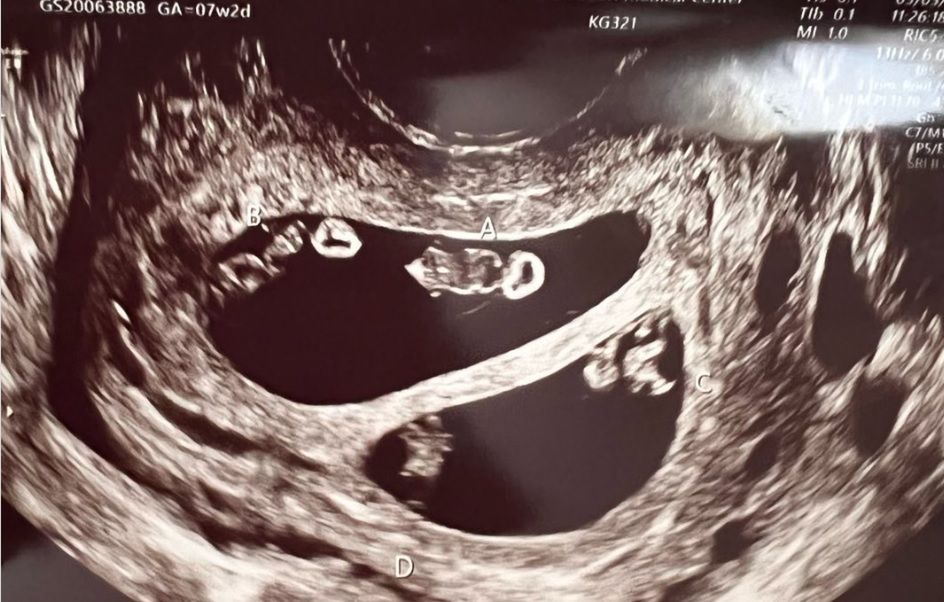

Jak się okazało, po wykonaniu badania USG, kobieta miała urodzić więcej niż jedno dziecko. Nie byłoby w tym nic dziwnego, gdyby nie fakt, że w jej brzuchu rozwijały się dwie pary bliźniaków. Wprawdzie takiego rodzaju ciąże się zdarzają, ale prawdopodobieństwo ich wystąpienia wynosi jeden na 10 milionów przypadków.

- Lekarz patrzył w monitor, później spojrzał się na nas i mówił ciągle "to niesamowite, jak to możliwe" - opowiada Ashley.

Podczas USG okazało się, że jest w podwójnej ciąży bliźniaczej

Podczas USG okazało się, że jest w podwójnej ciąży bliźniaczej © FB